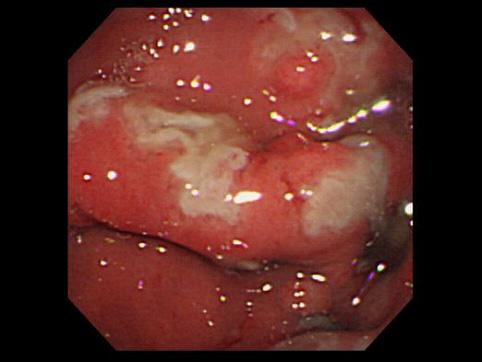

症例提示(所在地,施設名等): 福岡県・ 九州大学病院 (放射線科、鶴丸大介先生からの提供症例)

疾患(病理主体)の分類炎症性・潰瘍性疾患/肥厚性胃炎

部位(臓器別)胃(部位)/2つ以上

検査方法内視鏡

病変の最大径(ミリ)40以上